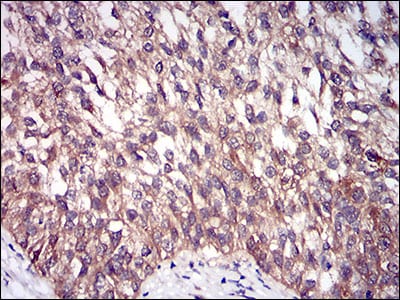

Immunohistochemical analysis of paraffin-embedded human endometrial cancer tissues using DIS3L2 mouse mAb with DAB staining.

Immunohistochemical analysis of paraffin-embedded human bladder cancer tissues using DIS3L2 mouse mAb with DAB staining.